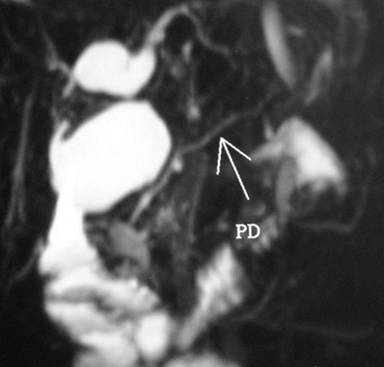

A 27-year-old female presented with a history, since childhood, of recurrent dull non-radiating upper abdominal pain, usually lasting for 2-3 days, occurring every 2-3 months and relieved with pain medications. She had been taking proton pump inhibitors, prokinetic agents and enzyme supplements for the previous 4 years. The current attack of abdominal pain was accompanied by fever and jaundice. Her total bilirubin was 14 mg/dL (reference range: 0.2-1.0 mg/dL), AST 100 IU/L (reference range: 15-48 IU/L), ALT 150 IU/L (reference range: 10-40 IU/L) and alkaline phosphatase was 280 IU/L (reference range: 40-120 IU/L). A computed tomography (CT) scan revealed a type I choledochal cyst with calcifications in the uncinate process of the pancreas (Figure 1). She had undergone common bile duct stent placement for her symptoms elsewhere but without relief of pain. Magnetic resonance cholangiopancreatography (MRCP) revealed calcifications in the region of the uncinate process of the pancreas, the presence of a type I choledochal cyst with dilatation of the right and left hepatic ducts at their confluence suggesting an anomalous pancreaticobiliary ductal junction with a common bile duct stent in place (Figure 2). There were no symptoms of endocrine or exocrine dysfunction and no pancreatic pain. She was referred to us for surgical consultation. Preoperatively, her total bilirubin had dropped to 1.7 mg/dL (direct 0.7 mg/dL; reference range: 0-0.2 mg/dL), ALT 16 IU/L, AST 31 IU/L, alkaline phosphatase 65 IU/L, gamma glutaryl transpeptidase (GGT) 31 IU/L (reference range: 0-60 IU/L); serum amylase and coagulation profiles were within normal limits. She underwent choledochal cyst excision with a Roux-en-Y hepaticojejunostomy. The procedure was uneventful. She has since been treated conservatively twice for symptoms of adhesive small bowel obstruction but has been asymptomatic for her primary disease during a follow-up period of 4 years.

Figure 2. MRCP showing a type I choledochal cyst, dilated right and left hepatic ducts and anomalous pancreatobiliary junction (PD: pancreatic duct). |